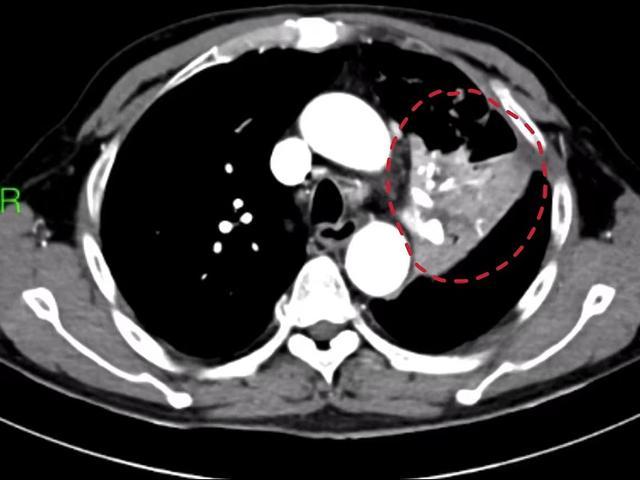

▲术前胸部CT显示患者出现左上肺脓肿(红圈内)

6月17日,杨大爷突然出现大咯血,一次咯血量高达200毫升。到湖南省人民医院检查发现,之前感冒导致的肺炎因为没有得到有效治疗,进一步进展成左上肺脓肿,还合并左下肺动脉假性动脉瘤,从而引发此次致命性大咯血。